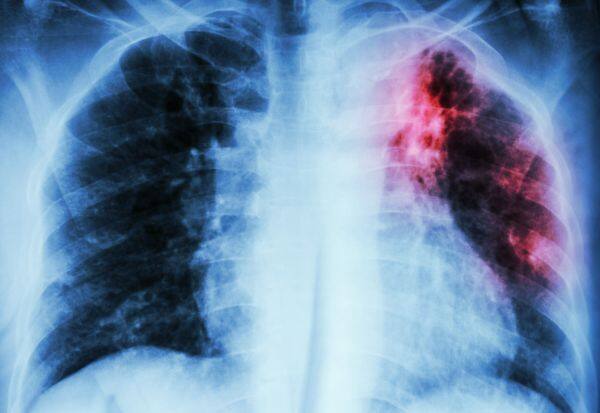

கோவை:கோவையில், 70 குழந்தைகள் உட்பட, 2,365 பேர் காசநோய் சிகிச்சை பெற்று வருகின்றனர். புதிதாக 125 பேர் இந்நோயால் பாதிக்கப்பட்டு இருப்பது, 100 நாள் சிறப்பு கண்காணிப்பு வாயிலாக கண்டுபிடிக்கப்பட்டுள்ளது.2030ல் காசநோயற்ற நாடாக அறிவிக்க திட்டமிட்டிருந்த நிலையில், புதிதாக அதிகரித்து வரும் தொற்று, சுகாதார பணியாளர்களுக்கு சவாலாக உருவெடுத்துள்ளது.

காசநோய் என்பது தலைமுடி, நகம் தவிர எந்த இடத்தில் வேண்டுமானாலும் வரலாம். நுரையீரலில் வரும் காசநோய், பரவும் தன்மை கொண்டது. தயக்கமின்றி சிகிச்சை எடுத்துக்கொள்ள வேண்டும்.

கோவையில், தனியார், அரசு மருத்துவமனைகளில் காசநோய் பாதிப்புக்காக சிகிச்சை எடுப்பவர்கள் எண்ணிக்கை, 2,365. இதில், 70 பேர் 15 வயதுக்கு உட்பட்ட குழந்தைகள்.